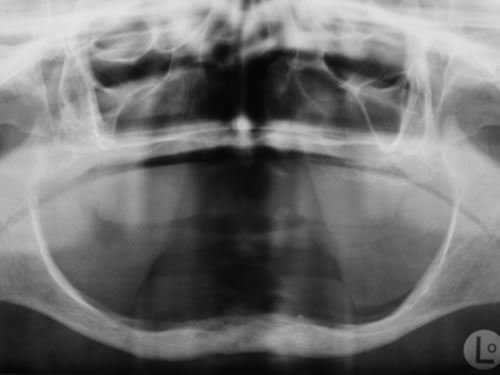

Auf die Möglichkeit, zahnlose Patienten mit Implantaten zuversorgen, wurde bereits in der Einleitung hingewiesen. Zunächst lässt sich nach einem vollständigen Zahnverlust in der Regel eine Prothese anfertigen, die einen guten Halt hat. Trotzdem empfehlen wir auch bei gutem Prothesensitz zu implantieren, da bei der Fehlbelastung durch den Prothesendruck derKieferknochen zurückgeht. Die Implantate sorgen für sehr guten Prothesensitz und schützen den Kieferknochen vor Knochenabbau. Häufig kommen die Patientenaber erst, wenn der Knochen weit abgebaut ist und der Prothesensitz sehr schlecht ist. In diesen Fällen wird das Implantieren deutlich schwieriger, da eine Mindesthöhe an Knochen als Implantatlager vorhanden sein muss (Abb. 3.1 bis 3.4).

Im Oberkiefer kann in den meisten Fällen ein guter Prothesensitzdurch einen Saugeffekt erzielt werden. Je weiter der Kieferknochen aber im Laufe der Jahre abgebaut wird, desto schwieriger wird es, einen ausreichendenHalt zu erzielen. Im Unterkiefer hat eine Prothese nach Knochenverlust auch bei sorgfältigstem zahnärztlichen Arbeiten und dem Einsatz aufwendiger Abform- und Registrierverfahren nur wenig Halt. Implantate sind für viele Patienten die letzte Hoffnung.